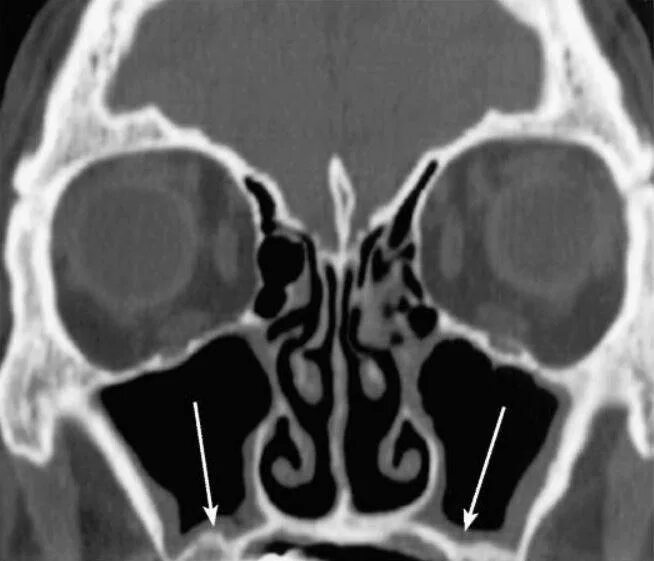

Утолщение верхнечелюстной пазухи что это значит